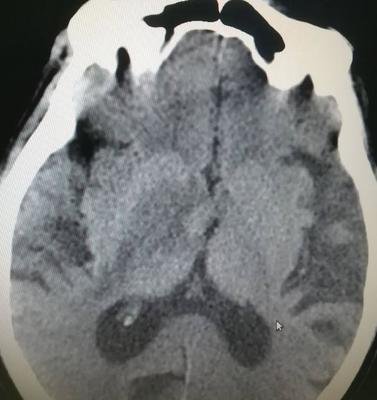

腦萎縮是指由各種原因?qū)е履X組織本身發(fā)生器質(zhì)性病變而產(chǎn)生萎縮的一種現(xiàn)象。病理上表現(xiàn)為腦組織體積縮小,細(xì)胞數(shù)目減少,腦室和蛛網(wǎng)膜下腔擴(kuò)大。對患者的正常生活造成極大的影響。那么引起腦萎縮的原因有哪些呢?

腦萎縮大多數(shù)考慮是由于神經(jīng)細(xì)胞變性所引起,患者一般表現(xiàn)為腦體積縮小,包括大腦萎縮和小腦萎縮?;颊咭部赡苁怯捎陂L期失眠或者是壓力大引起,也可能是長期大量飲酒引起。

腦萎縮最主要的致病因素是腦血管長期慢性缺血、缺氧狀態(tài),腦細(xì)胞形態(tài)及功能受到影響,即形成腦萎縮。因此,如果患者有長期慢性腦供血不足時,就可能會出現(xiàn)腦萎縮。也可能是一種老年性的腦改變。患者可以無任何臨床癥狀和體征,嚴(yán)重時可以出現(xiàn)頭暈,也可以出現(xiàn)意向性震顫,也可能會出現(xiàn)記憶力下降,甚至可能會出現(xiàn)癡呆等等。